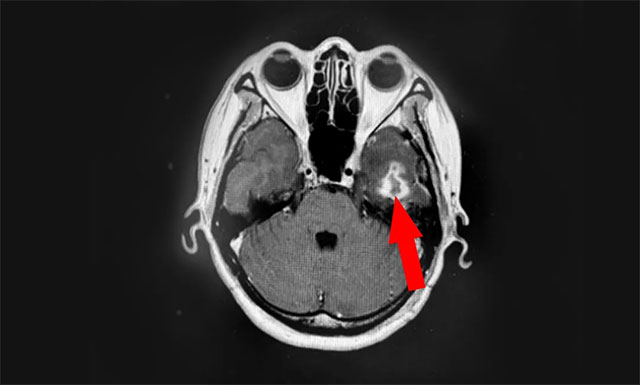

近期,患者为寻求进一步治疗,来到上海蓝十字脑科医院。医院肿瘤科(放疗)头部伽玛刀组主任陈琦及医生团队结合患者病情变化,为汤女士行立体定向穿刺引流联合伽玛刀治疗。经一段时间住院恢复后复查,病灶占位较前进一步缩小,肿瘤进展得到了较好地控制,目前已顺利出院。

▲ 伽玛刀治疗后复查,可见病灶占位明显缩小